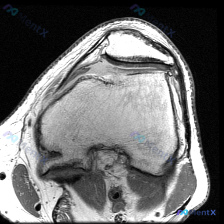

刚看到这个病例,是临床怀疑膝关节软骨异常,只提供了一张膝关节髌股关节层面的轴位T1加权MRI,整理一下分析思路分享给大家。 一、病例与影像基本信息 本次仅提供单张膝关节MRI轴位T1序列影像,临床核心疑问是评估是否存在软骨异常,未提供患者病史、症状及其他临床资料,也未提供其他序列/切面的MRI影像。...

今天看到这个挺有讨论价值的读片问题,整理了完整信息和分析思路分享给大家。 病例/影像基本信息 这是一张膝关节轴位T1加权MRI图像,临床提出的问题是评估是否存在软骨异常。 我们先看这份影像的客观观察结果: 1. 整体解剖结构:髌骨、股骨远端滑车轮廓清晰,皮质骨光滑,无骨质破坏或骨皮质中断,骨髓信号大...

今天碰到一个很典型的临床判断和影像结果矛盾的情况,整理一下完整分析思路跟大家交流一下。 病例核心信息 这是一张膝关节MRI的轴位T1加权像,信息整理如下: - 骨骼结构:髌骨、股骨远端滑车区骨皮质连续,骨髓信号均匀,未见骨破坏或异常信号,髌骨关节软骨面轮廓正常 - 髌股关节:关节间隙可见,软骨表面清...

最近遇到一个有意思的读片病例:临床怀疑髌股关节软骨异常,但给出的单张T1加权轴位MRI却没看到明确病灶,整理一下整个分析思路分享给大家。 一、病例影像基础信息 这是一份膝关节MRI检查的T1加权轴位(横断面)图像,扫描层面位于髌股关节水平,先整理一下基础读片结果: 1. 解剖结构确认:前方为髌骨,后...